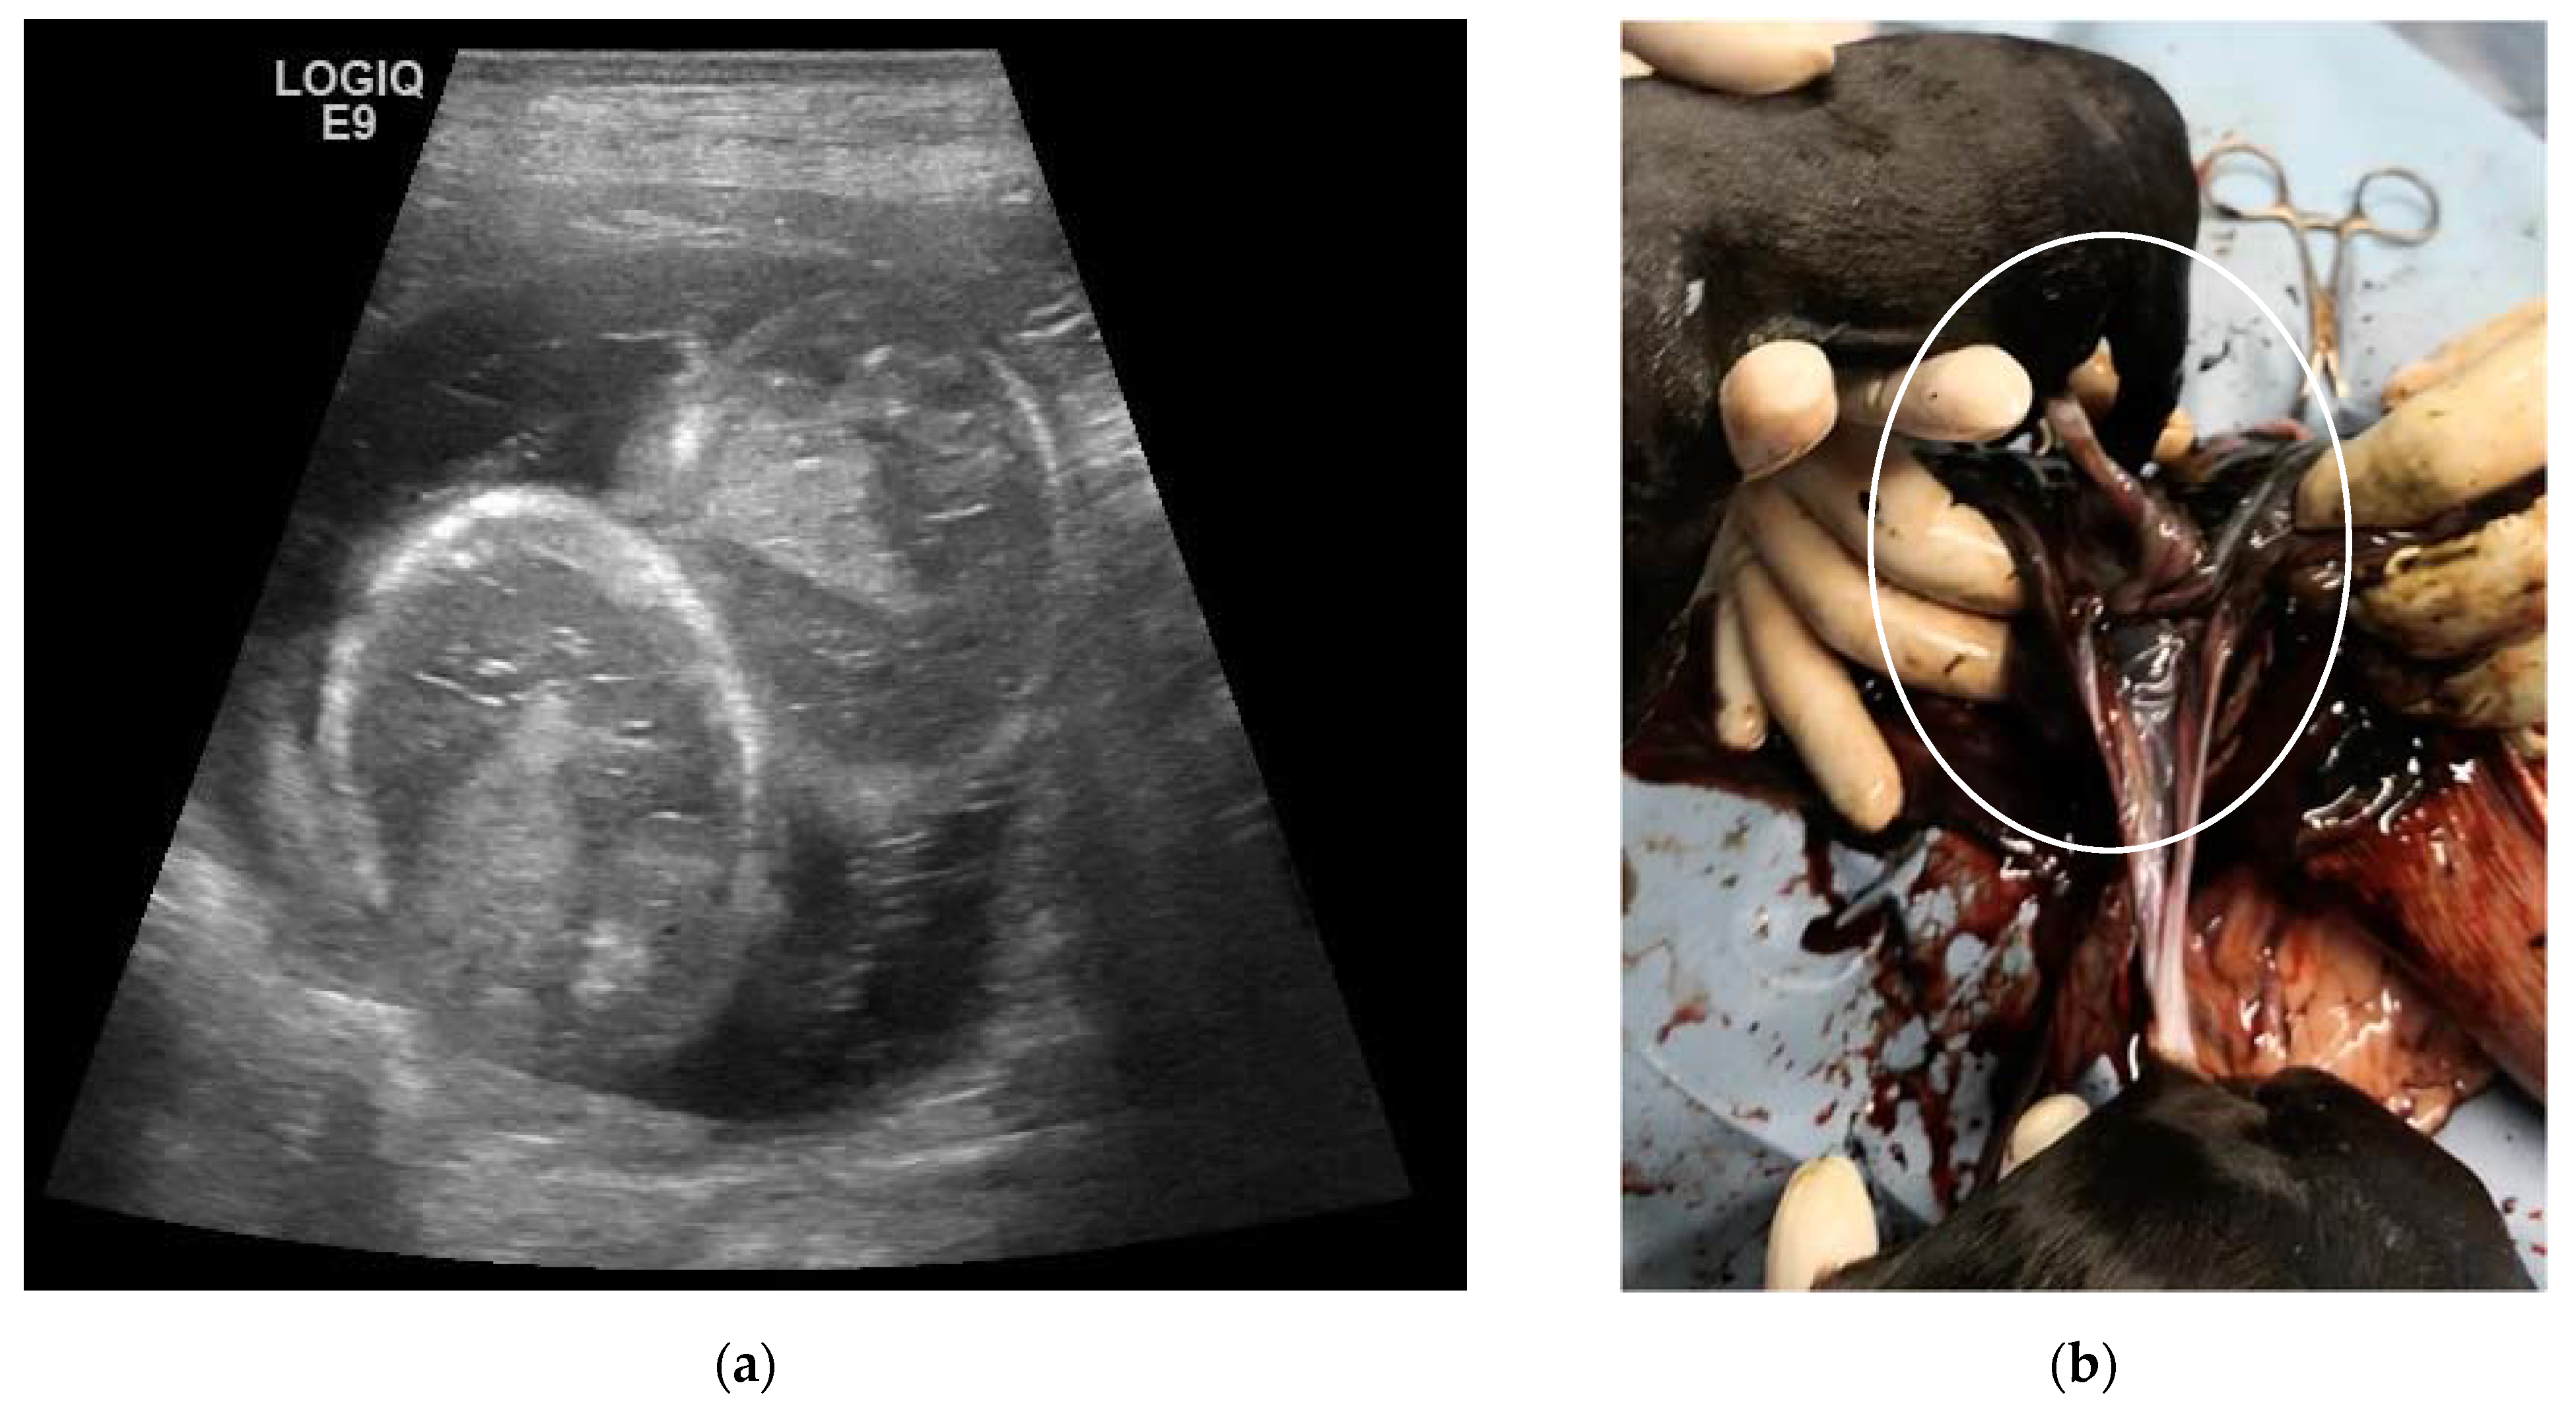

| 4C | 5-year-old Labrador Retriever female dog | 25, 32, 39, 46 and 53 | 10 | Monochorionic twins, morphologically comparable to the other embryos/foetuses. | C-section. Twins of different sex, alive, with partial twisting of the umbilical cord. One stillborn, two puppies euthanatized for malformations. | Death of the male twin after 7 days of hypoglycaemia and dehydration. |